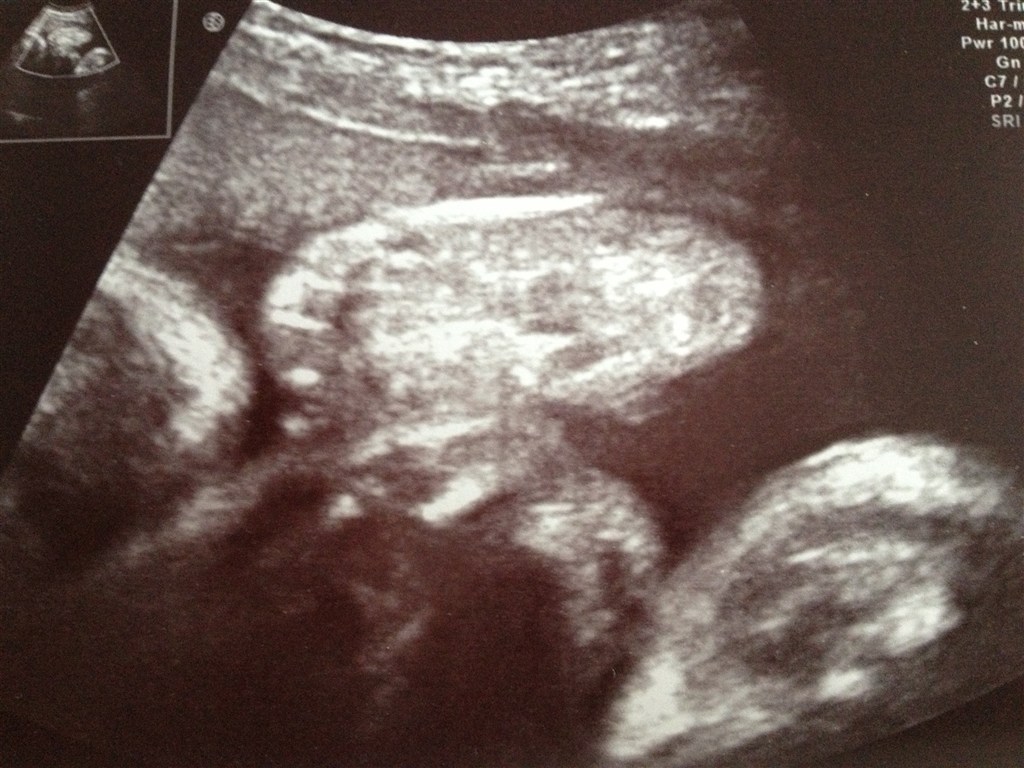

Det ville Baby B dog ikke. Hun blev ved med at gemme sig bag armen, så vi fik et billede af hendes fod i stedet for